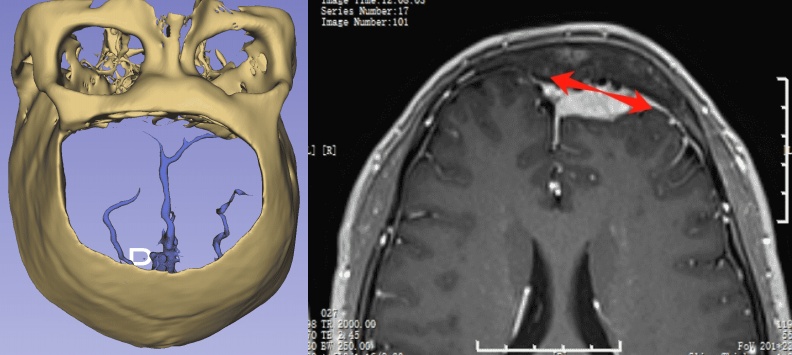

腫瘤與靜脈、矢狀竇的關系

靜脈影像重建

CT重建

左額內外板可見骨質增生

■ 初步診斷:左額部凸面-矢狀竇旁腦膜瘤

■ 先行瘤內部分減壓,然后沿中線探查腫瘤與矢狀竇關系,進一步切斷腫瘤血供

■ 瘤體縮小后,沿腫瘤與腦組織/血管蛛網膜界面分離,逐漸分塊切除腫瘤

■ 過程中保護周圍正常腦組織及正常皮層引流靜脈